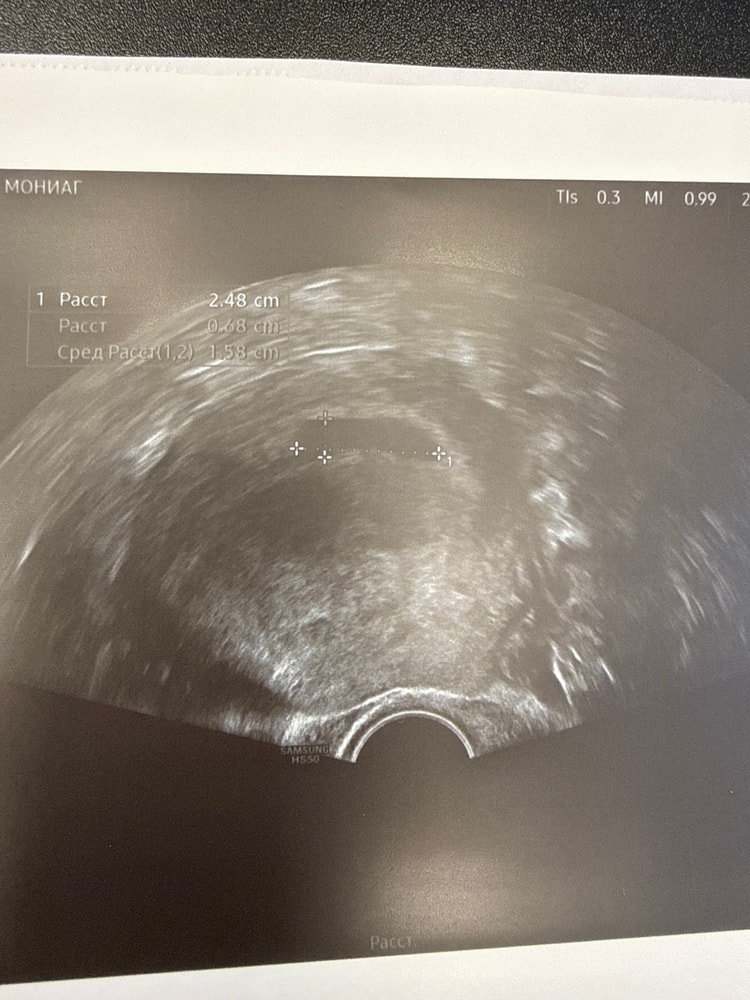

делали узи на 21 дпп - было ПЯ и ЖМ

узи на 27 дпп - ЖМ, эмбрион и пульсация

узи на 21 дпп - нет ничего … плодной яйцо и всё… отправили на контрольное узи по месту жительства для госпитализации и чистки ….